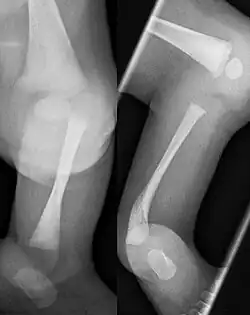

Eine Tibiale Hemimelie oder ein Tibialer Längsdefekt bezeichnet das angeborene Fehlen (Aplasie) oder die Unterentwicklung (Hypoplasie) der Tibia. Sie kann isoliert, häufiger aber in Verbindung mit Fehlbildungen am Fuß medial sowie einer Varusstellung im Rückfuß einhergehen.[1]

Einteilung

Für die Behandlung gebräuchlich ist die Klassifikation nach Kalamchi und Dawe:[6]

- Typ I Aplasie der Tibia, Fuß adduziert, + eventuell fehlende Strahlen medial

- Typ II Tibia nur distal fehlend, Artikulation zum Femur erhalten

- Typ III Dysplasie der Tibia distal mit tibiofibulärer Diastase (Fehlanlage der Sprunggelenksgabel)

Bereits im Mutterleib kann während einer Ultraschalluntersuchung die Fehlbildung erkannt werden,[2] die Verkürzung und Fehlstellung des Unterschenkels ist nach der Geburt offensichtlich. Ein Röntgenbild kann das Ausmaß der Fehlbildung sowie zusätzliche knöcherne Veränderungen dokumentieren. Mittels Sonographie können die knorpeligen Anlagen und deren Stellung zum Gelenk sicher dargestellt werden, wesentlich bei den Typen II und III.